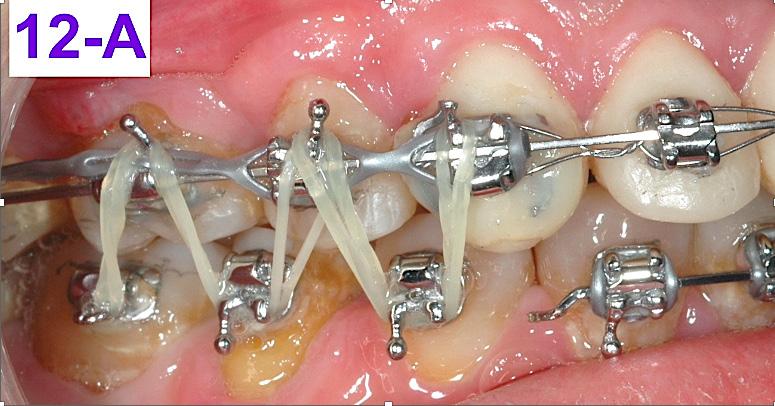

cut and bent in, just distally to the cuspids. Also, two 3/8” – 2.5 oz. elastics were placed, in a letter “W” with tail configuration, for one month. They were zig-zagged from the maxillary cuspids and finished on the mandibular molars and had a slightly protrusive line of action on the mandible (Figure 12 - A, B).10

FIG. oral mucosa FIG. 9C: Tissue guard, right lateral view FIG. 9D: Protraction of the first molar, left lateral view FIG. 10A: Lingual intra – Power thread, occlusal view FIG. 10B: Class II elastic, right lateral view FIG. 10C: Triangular elastic, left lateral view FIG. FIG. FIG. 12A: “W” with tail, right lateral view FIG. 12B: “W” with tail, left lateral view